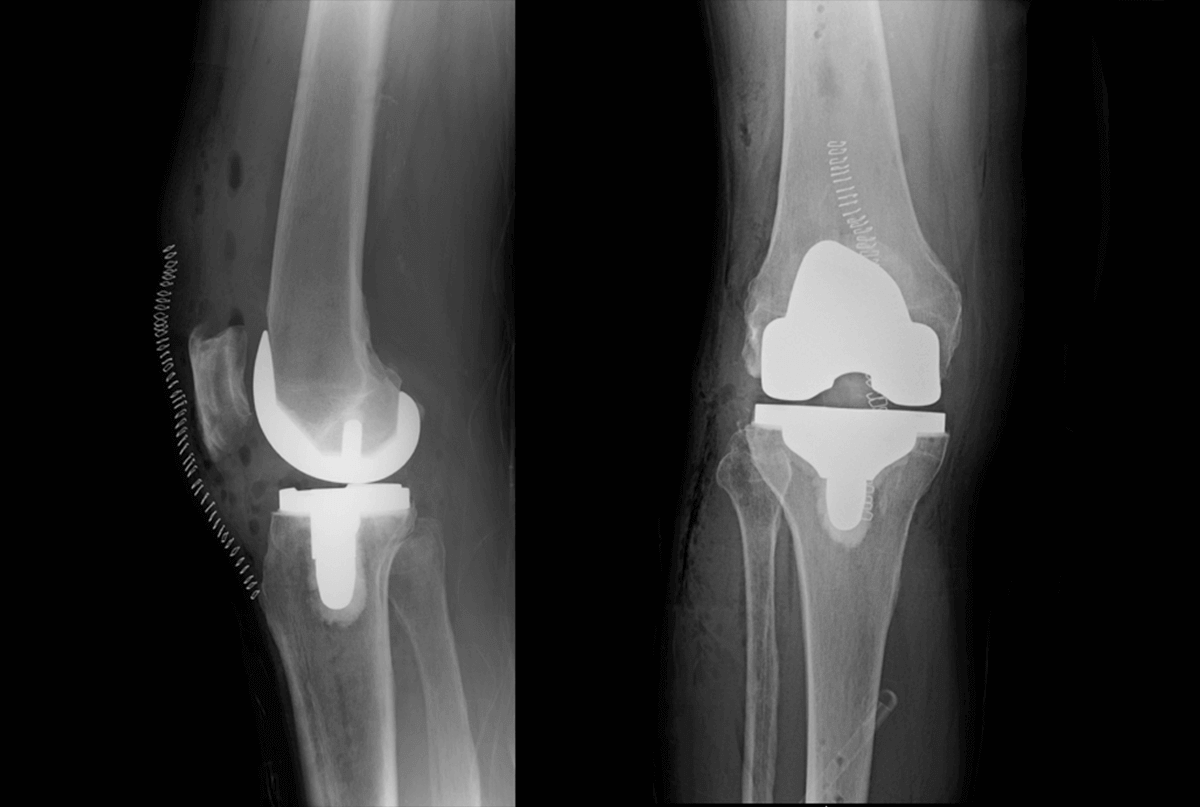

• Total knee replacement

ADVANCED JOINT REPLACEMENT

Our total hip, knee, and shoulder replacements are performed using modern surgical techniques designed to minimize tissue disruption and support early mobility. Patients return home the same day with a clear, structured recovery plan.